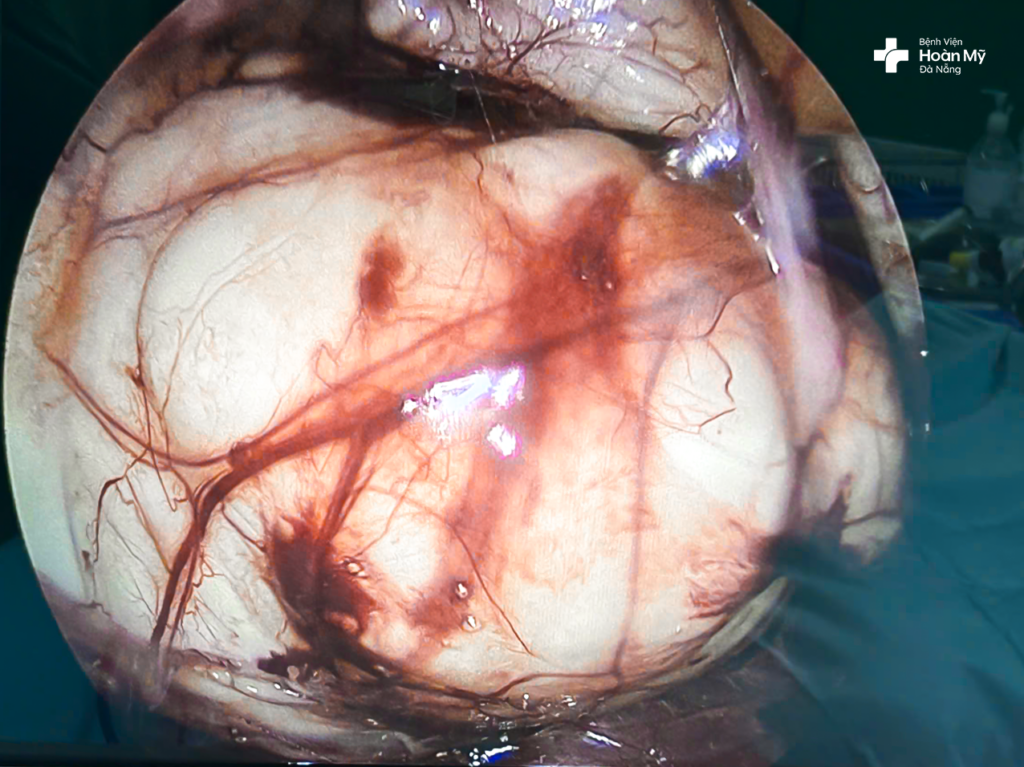

BS.CKI. Bùi Quốc Triệu – Trưởng khoa Ngoại Tiết niệu – Nam khoa, Bệnh viện Hoàn Mỹ Đà Nẵng chia sẻ: "Đây là khối u nang sau phúc mạc trái, kích thước lớn 150 x 180 mm và khá hiếm gặp. Khối u choán gần như hết nửa trái khoang bụng, chứa dịch đã chèn ép tạng ổ bụng, đẩy thận trái lên cao. Trong quá trình bóc tách nhận thấy đây là một khối u nang chứa dịch trắng đục hướng đến u nang bạch huyết dưỡng chấp, bác sĩ phải rất cẩn thận để loại bỏ hoàn toàn khối u để tránh tái phát và ngăn ngừa biến chứng xì dò hạch bạch huyết sau phẫu thuật. Nếu phẫu thuật cắt hoàn toàn nang mà không tổn thương các cơ quan lân cận, nguy cơ tái phát rất thấp."

Ekip mất hơn 1 giờ 30 phút tiến hành phẫu thuật nội soi sau phúc mạc bóc khối u nang với 3 lỗ trocar. Quá trình bóc tách khá thuận lợi như dự kiến, nhưng do kích thước quá lớn nên các bác sĩ đã tiến hành chọc hút chủ động sau đó bóc trọn vẹn màng u mà không ảnh hưởng đến các cơ quan lân cận. Về đại thể hút ra 2,7 lít dịch dạng sữa đục, xét nghiệm dịch vô trùng, chứa nhiều tế bào lympho, màng u cũng được gửi làm giải phẫu bệnh lý và cho về kết quả lành tính.

(hình 2) Hình ảnh khối u nang sau phúc mạc trong phẫu thuật